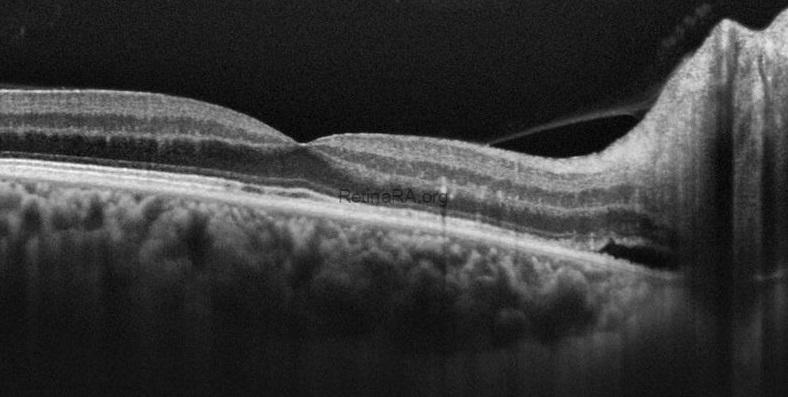

On the 20th day of treatment, the visual acuity of the right eye improved to 20/20, and serous macular detachment completely resolved. RNFL edema decreased and residual subretinal fluid was seen adjacent to the optic disc.